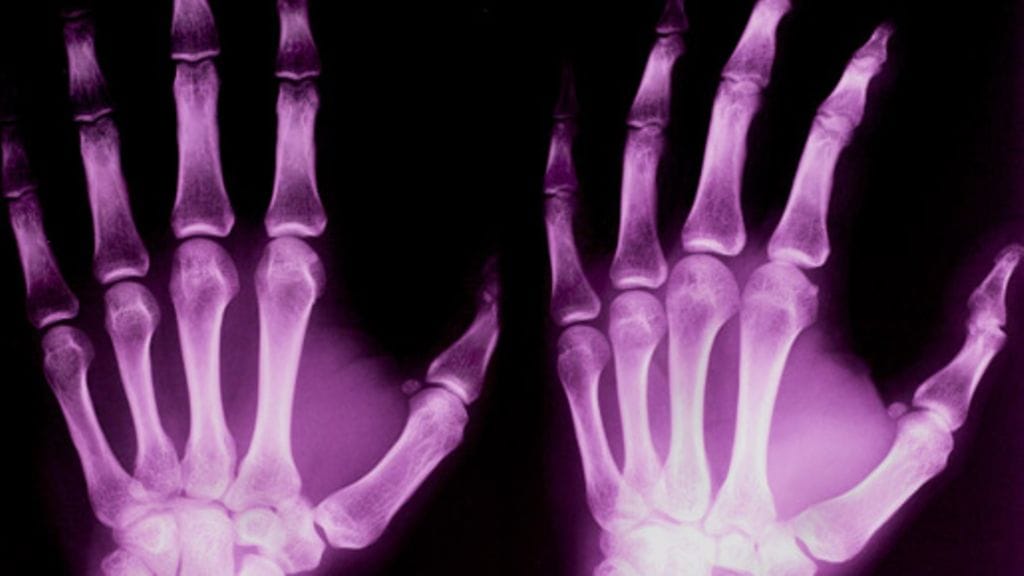

Vaikka kaikkien luusto haurastuu, joidenkin ihmisen luiden lujuus vähenee siinä määrin, että nopea haurastuminen diagnosoidaan osteoporoosiksi. Tautia sairastaa yli 400 000 suomalaista. Osteoporoosi altistaa luumurtumille, joiden kanssa ei ole leikkimistä.

Osteoporoosi on "hiljainen epidemia", sillä se ei juuri ilmoittele tulostaan – se huomataan yleensä vasta, kun jo luunmurtuman saanut potilas passitetaan luuntiheysmittauksiin riskitekijöiden kartoituksen jälkeen. Tuppuraisen mukaan hälytyskellojen pitäisikin soida, jos jo viisikymppinen joutuu kärsimään esimerkiksi rannemurtumasta.